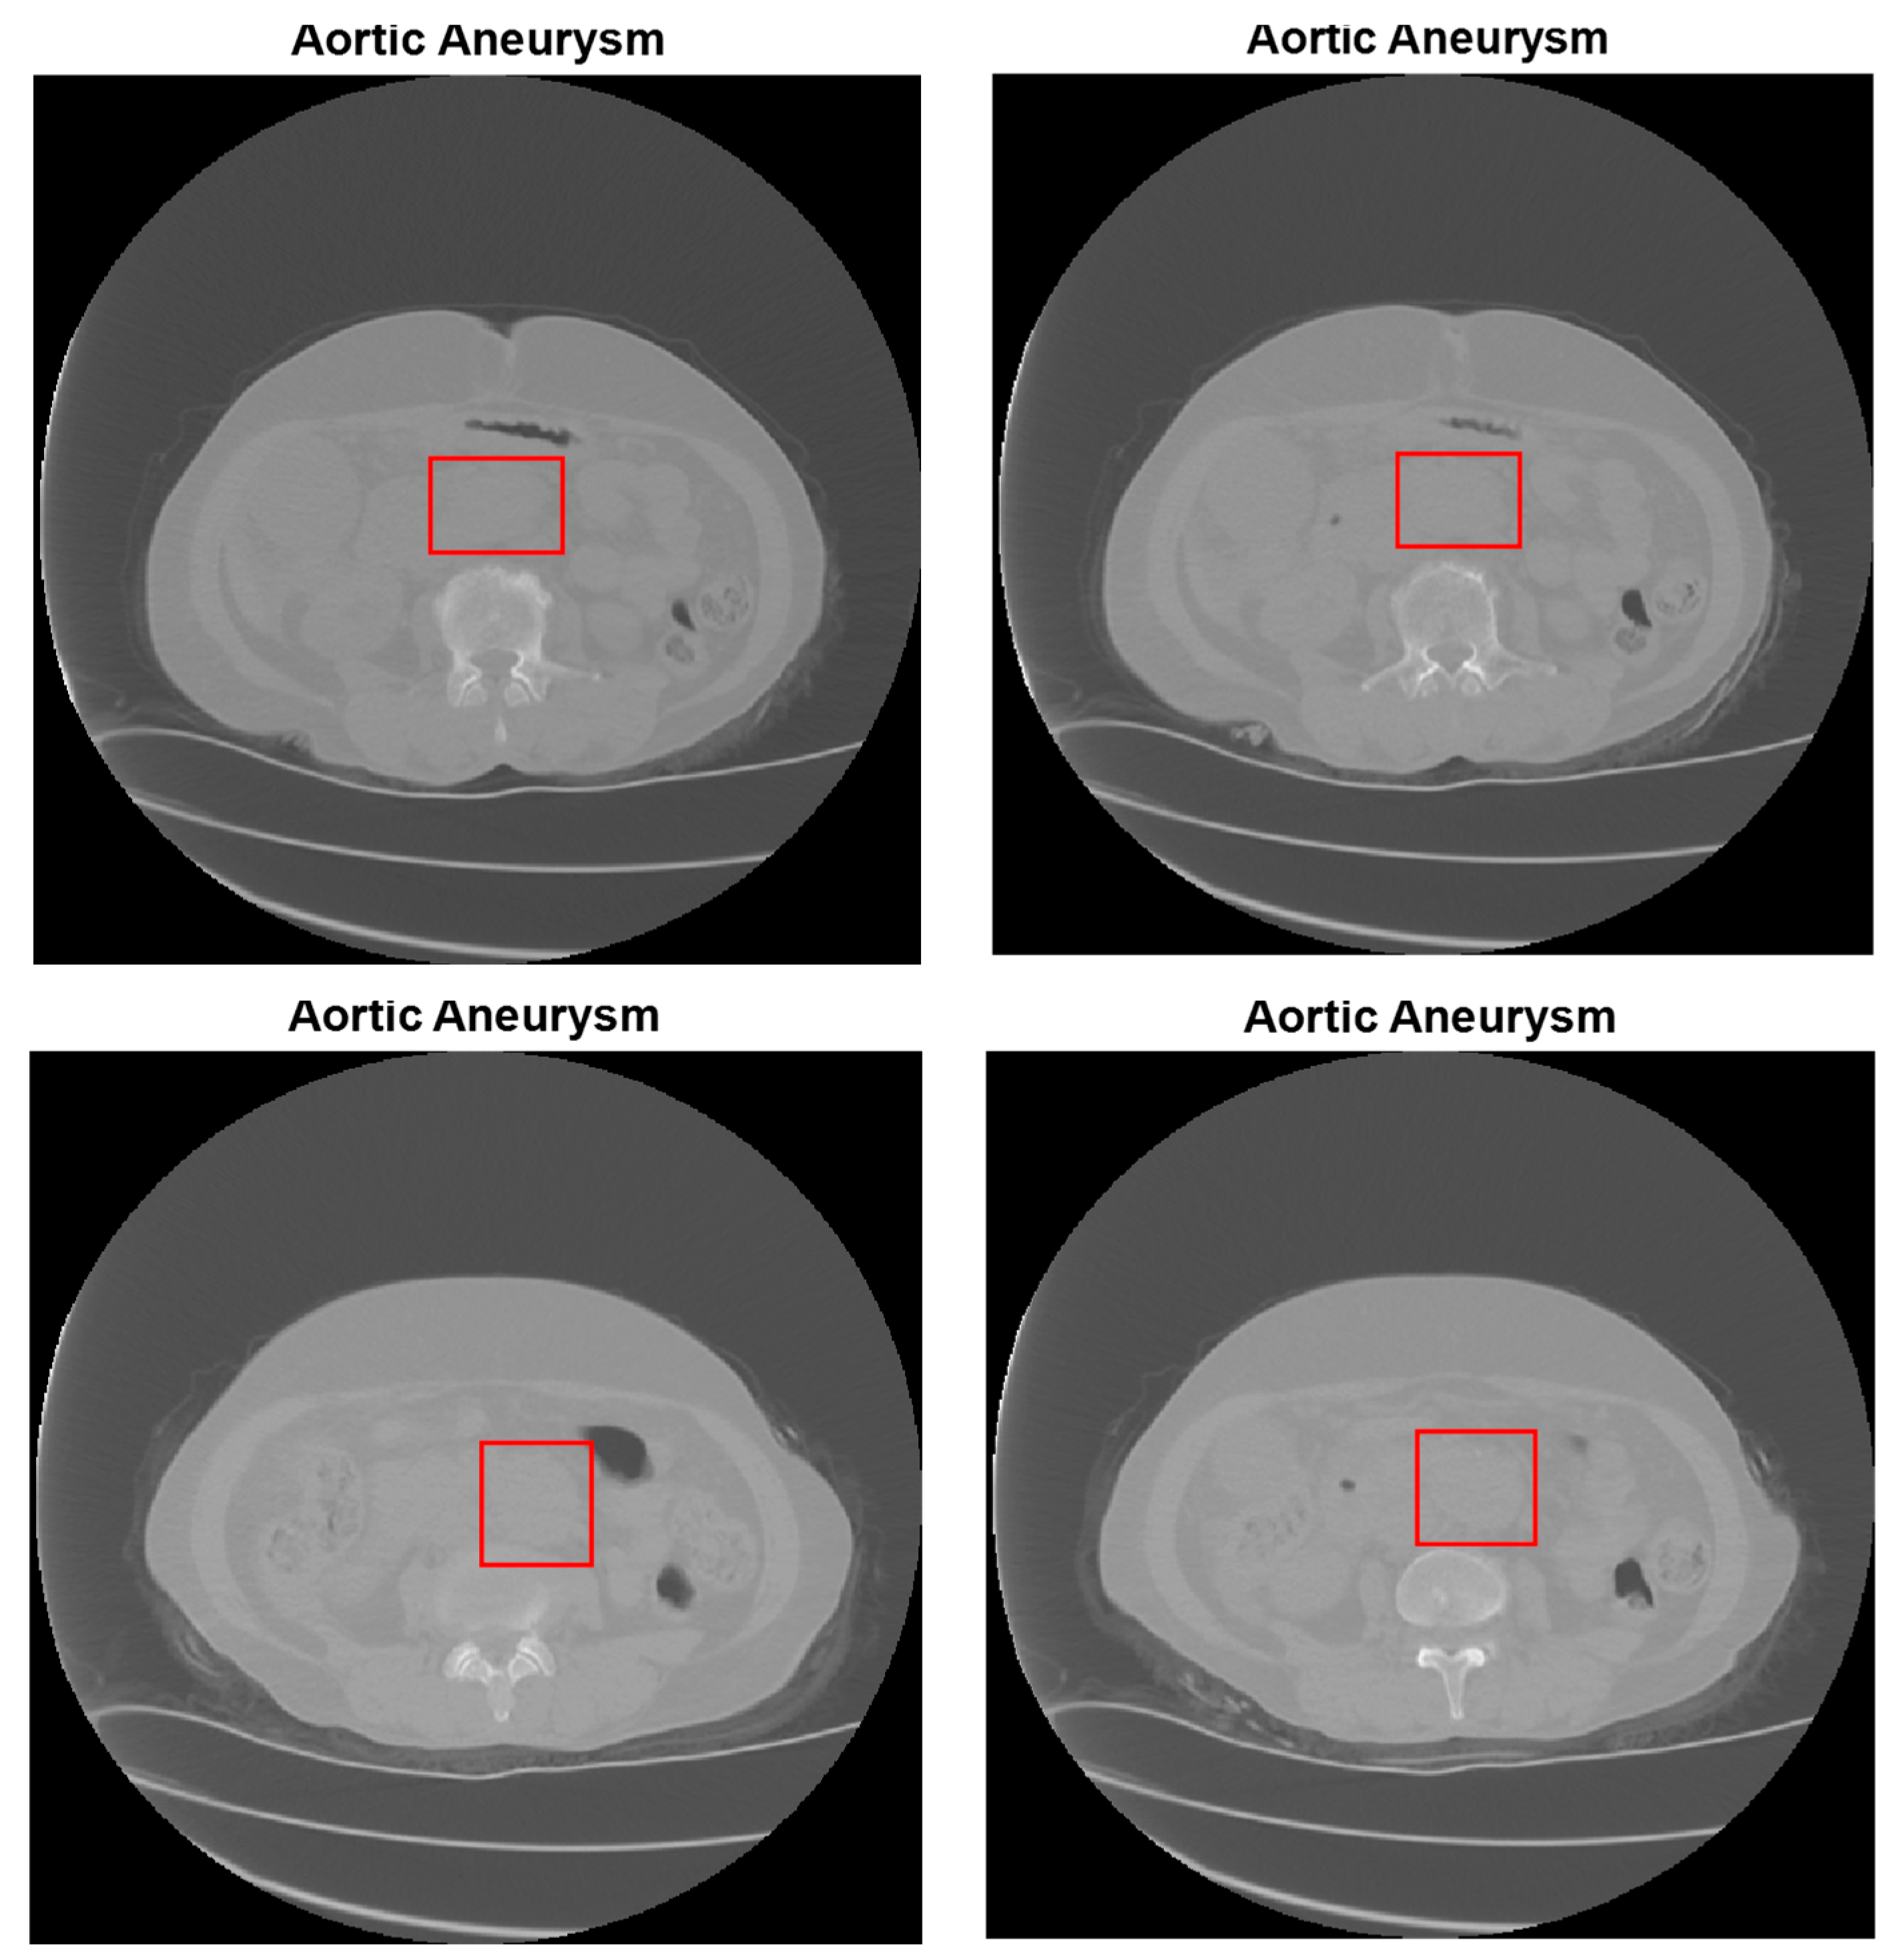

2.2. Abdominal Aortic Aneurysm (AAA) Detection